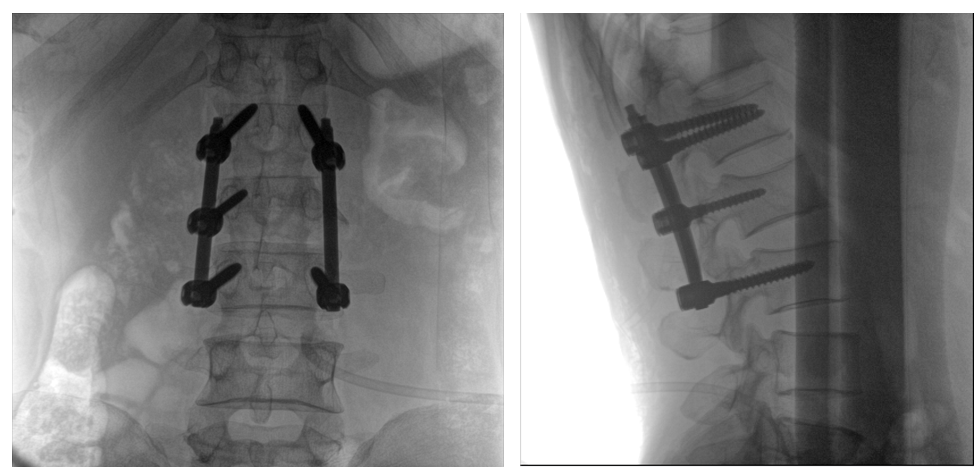

病例一:

患者不慎摔伤,伤后腰部疼痛,腰2椎体压缩性骨折,遂以“椎弓根钉内固定术”治疗。椎弓根螺钉可以从椎体后方贯穿到椎体前方,达到椎体三柱固定,但是手术过程中要保对多节锥体进行手术,所以要求图像要尽可能的展现出全节段腰椎。

一体式C形臂全节段腰椎临床影像

普爱医疗PLX119C大平板一体式C形臂采用30CM×30CM的平板探测器,一般可一次性成像5节腰椎,呈现更广阔的视野。使医生一次性全面地观察到伤椎及周围椎体情况,使得手术效率更高、更准确。